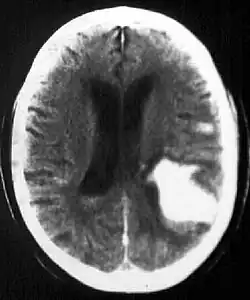

In the elderly population, amyloid angiopathy is associated with cerebral infarcts as well as hemorrhage in superficial locations, rather than deep white matter or basal ganglia. These are usually described as "lobar". These bleedings are not associated with systemic amyloidosis.

Cerebral amyloid angiopathy may cause intraparenchymal hemorrhage even in patients without elevated blood pressure. Unlike hypertension, cerebral amyloid angiopathy does not typically affect blood vessels to deep brain structures. Instead, it is most commonly associated with hemorrhage of small vessels in the cerebral cortex.[2] The strongest risk factor for intraparenchymal hemorrhage associated with cerebral amyloid angiopathy is old age, and cerebral amyloid angiopathy is most frequently seen in patients who already have, or will soon be diagnosed with, dementia.[3]

Computed tomography (CT scan): A CT scan may be normal if it is done soon after the onset of symptoms. A CT scan is the best test to look for bleeding in or around your brain. In some hospitals, a perfusion CT scan may be done to see where the blood is flowing and not flowing in your brain.